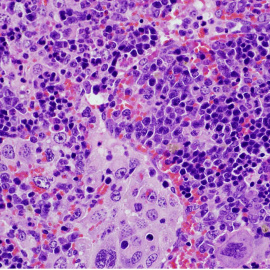

Hallada una mutación genética clave en la aparición de linfomas y en el cáncer de pulmón

Imagen de microscopía de un bazo que presenta un linfoma desarrollado por ratones que expresan una mutación oncogénica en el gen VAV1.